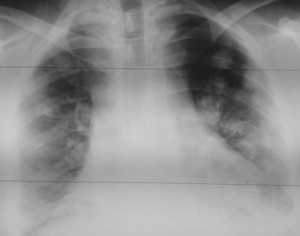

Как выглядят метастазы в легких на рентгене? Слева — узловые образования у пациента с раком яичка. Справа - метастазы рака яичников гематогенного характера с выраженным опухолевым лимфангиитом (обратите внимание на деформированный сетчатый, линейный характер легочного рисунка).